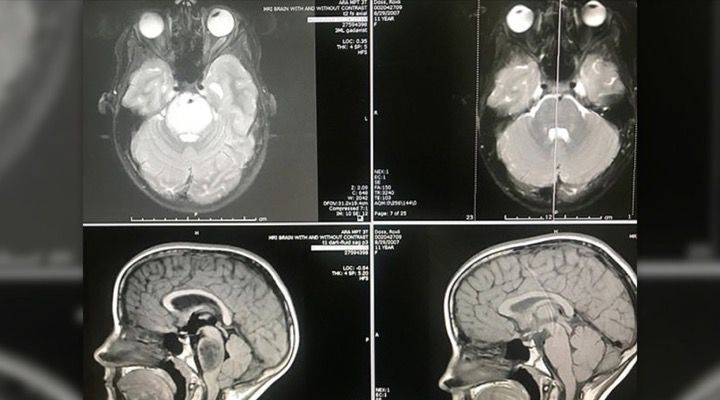

Actually Unbelievable

After six full weeks of radiation, despite the dire prognosis, Roxli was given an MRI and then went to visit her doctor, Dr. Harrod a few days later. “When I first saw Roxli’s MRI scan, it was actually unbelievable,” said Dr. Harrod. The tumor had totally disappeared and medical professionals, while ecstatic, were left scratching their heads in disbelief.

Spontaneous Regression